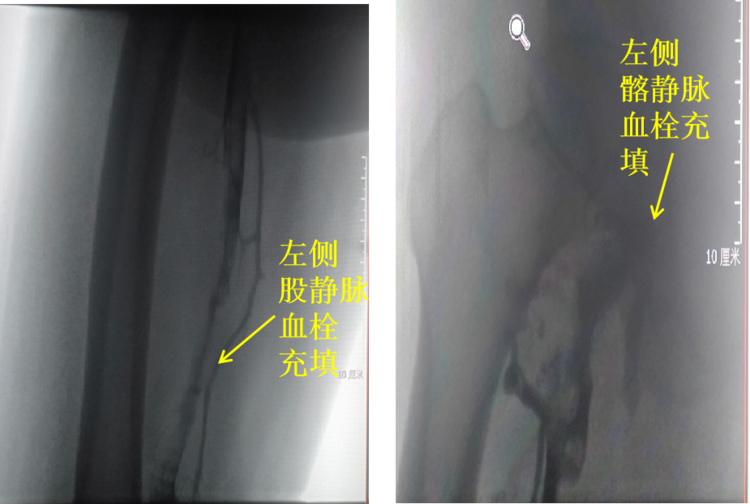

患者入院后,完善相关检查,超声提示:左下肢深静脉全程血栓形成。初步诊断:左下肢深静脉血栓形成(混合型 ),先给予抗凝、溶栓治疗3天后效果不佳,患者左下肢肿胀未明显消退。不排除左侧Cockett综合征及下肢深静脉大量血栓可能,经讨论后决定在DSA下行下腔静脉造影+滤器植入+Angiojet机械祛栓术备左髂静脉球囊扩张及支架置入术。患者取右侧腹股沟股静脉穿刺成功后,植入下腔静脉临时滤器后,然后经左侧腘静脉行Seldinger法穿刺,造影确认左侧髂股静脉全程血栓。

祛栓后造影,左髂股静脉较术前明显通畅,存在左侧髂静脉压迫综合征(Cockett综合征)。